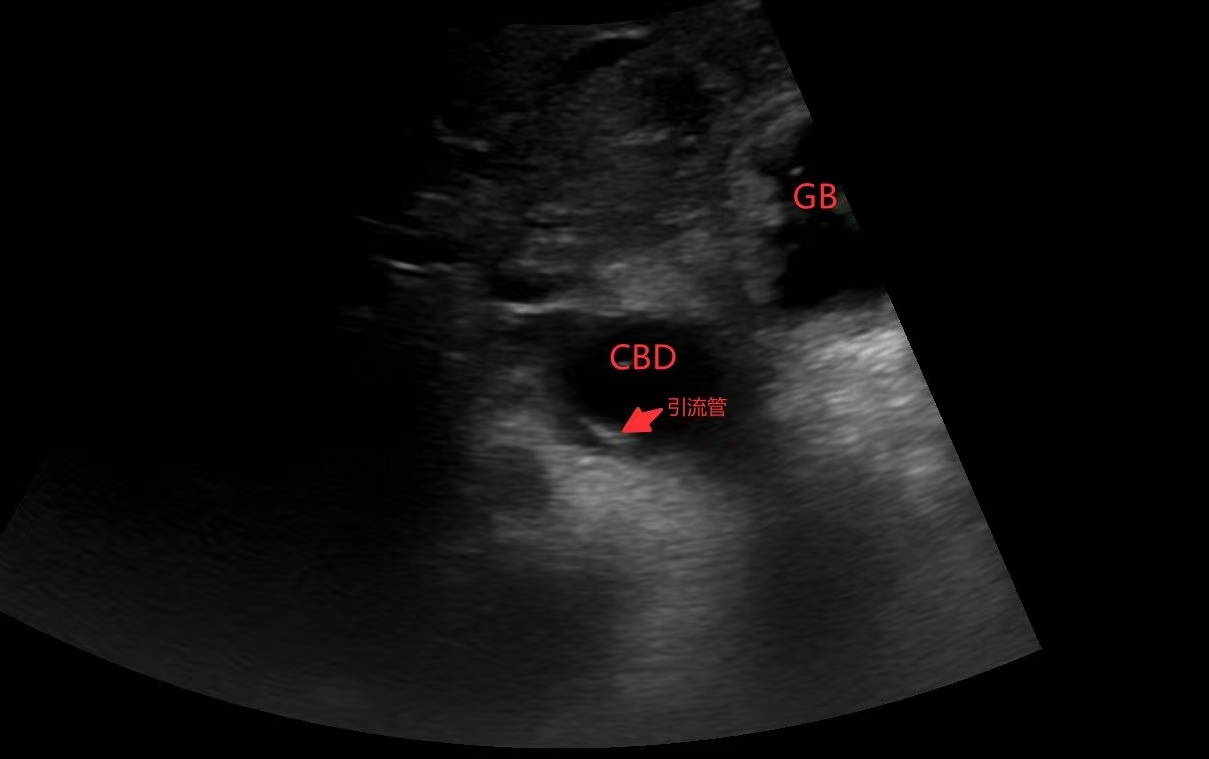

在ICU治疗期间,患者再次发热,胆红素持续升高,床旁彩超显示胆总管扩张达2.6cm,肝内胆管亦见扩张,提示重度胆道梗阻,病情危急。重症医学科联合超声科、普外科开展多学科会诊,经充分评估并与家属沟通后,团队一致决定实施超声引导下PTBD术,以微创方式实现胆汁引流。

手术中,超声科李莉医师在普外科张自飞医生协助下,凭借精准超声定位,清晰显示肝内扩张胆管,实时引导穿刺针准确刺入目标胆管,成功置入引流管,引流出白胆汁。整个操作微创、高效,过程顺利,患者生命体征平稳。术后引流通畅,黄疸逐步消退,感染指标下降,病情明显改善。